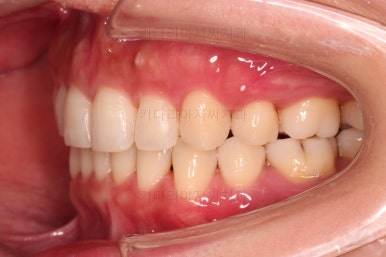

공간, 교합, 중앙선 모두 매우 좋아지고 있습니다.

윗니 한 쪽만 왜소치여서 100% 중앙선을 못맞추는 건 환자분 본인도 잘 아시는데요.

그래도 할 수 있는데까지 해보기로 했습니다.

중앙선도 처음보다 매우 좋아진 양상입니다.

옆모습도 큰 변화없이 양호하게 진행중이고요.